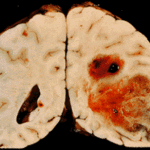

I ricercatori hanno scoperto e convalidato un esame del sangue in grado di predire con precisione superiore al 90 per cento, se una persona sana svilupperà deterioramento cognitivo lieve o morbo di Alzheimer, entro tre anni.

Il test identifica 10 lipidi, o grassi, nel sangue che predicono l’insorgenza della malattia. Potrebbe essere pronto per l’uso in studi clinici e altri usi diagnostici possibili, in soli due anni, secondo i ricercatori.

Nel terzo anno dello studio, i ricercatori hanno selezionato 53 partecipanti che hanno sviluppato aMCI / AD (di cui 18 convertitori) e 53 cognitivamente normali, per controlli appaiati durante la fase di scoperta dei biomarker lipidici. I lipidi non sono stati mirati prima dell’inizio dello studio, ma piuttosto, sono un risultato dello studio. I ricercatori hanno scoperto 10 lipidi che sembrano rivelare la composizione delle membrane cellulari neuronali nei partecipanti che sviluppano sintomi di deficit cognitivo o AD. Il pannello è stato successivamente convalidato utilizzando i restanti 21 partecipanti aMCI / AD (di cui 10 convertitori), e 20 controlli. I dati sono stati analizzati per verificare se i partecipanti potevano essere assegnati alle corrette categorie diagnostiche, utilizzando esclusivamente i 10 lipidi identificati nella fase di scoperta.